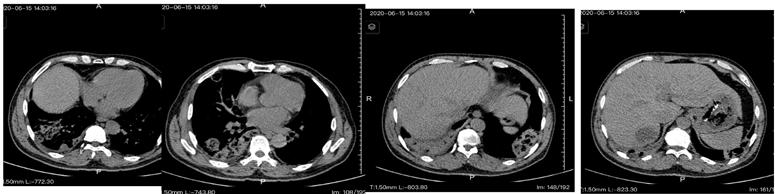

肺动脉CTA影像(图二)